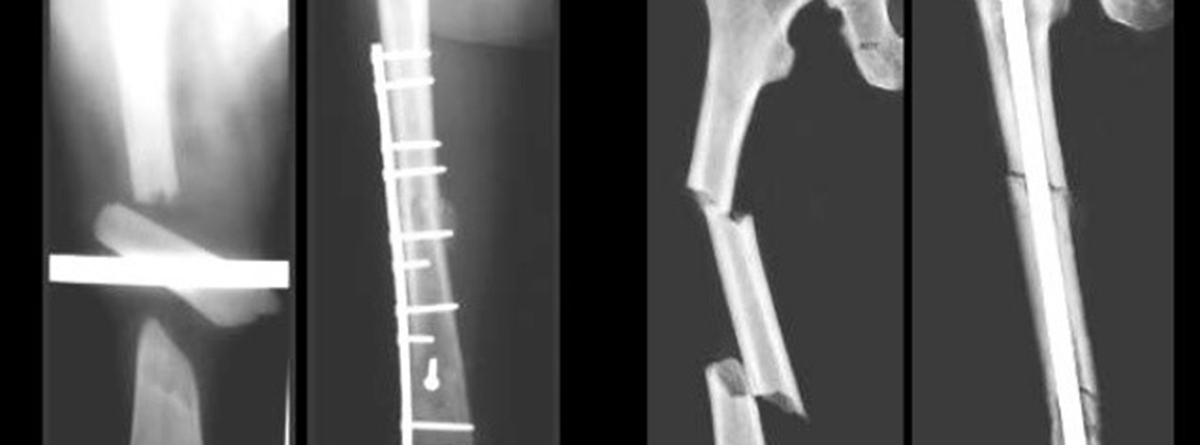

Tratamiento de Fracturas

¿EN QUÉ CONSISTE EL TRATAMIENTO DE FRACTURAS?:

En el tratamiento de fracturas, las técnicas quirúrgicas y anestésicas cada vez más novedosas permiten una mejor recuperación. Modernos equipos de imágenes intraoperatorias, nuevos materiales quirúrgicos y procedimientos complementarios permiten mejores resultados con una mínima cicatriz.